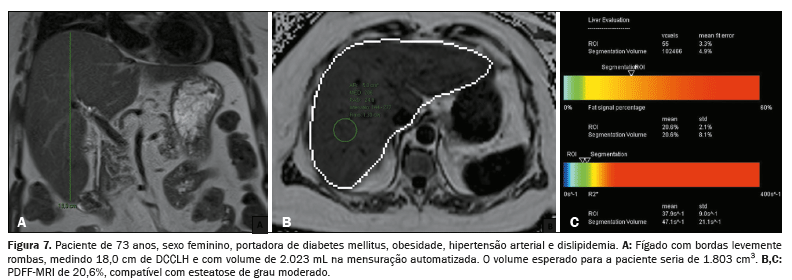

A associação, tanto do DCCLH e a PDFF-MRI (rs = 0,474;

p < 0,001) quanto da Voe e a PDFF-MRI (rs = 0,568;

p < 0,001), apresentou correlação estatisticamente significante, refletindo os resultados das análises anteriores (Figura 5). A relação entre o acúmulo de gordura e o aumento do volume hepático está exemplificada nas Figuras 6, 7 e 8.